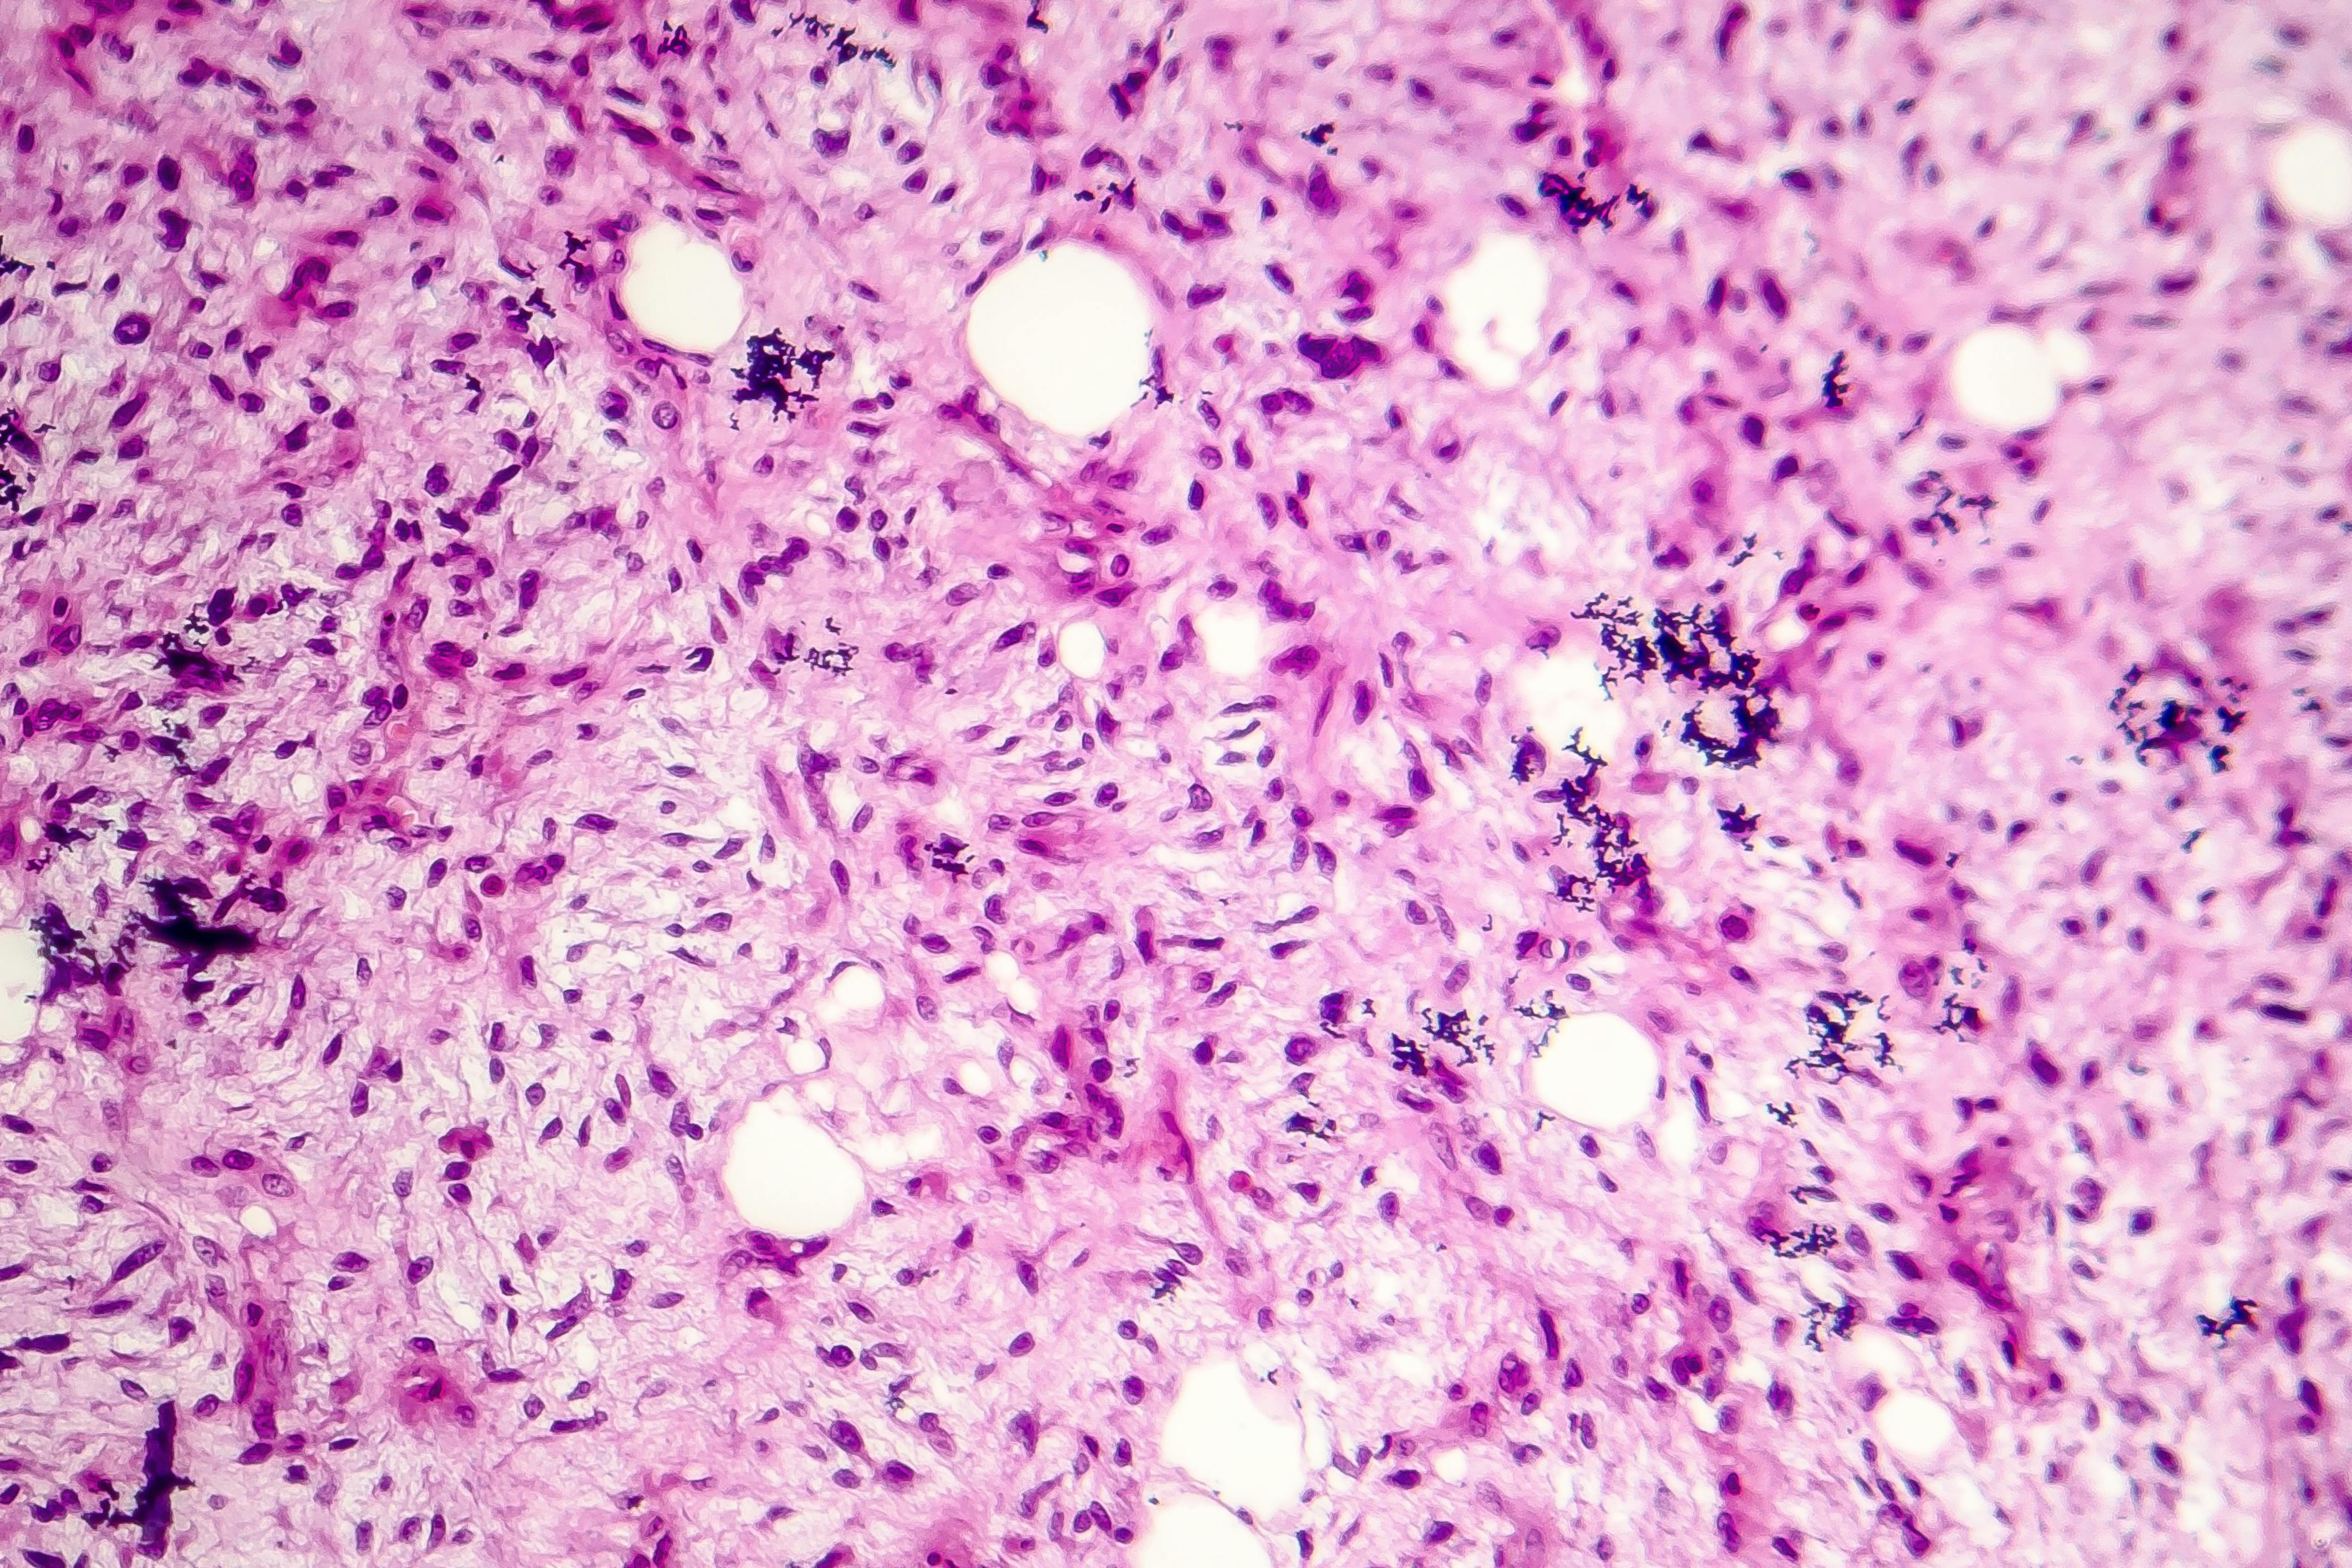

Difficult diagnoses of soft tissue tumor aided by immunohistochemical surrogates

Immunohistochemistry (IHC) can serve as a powerful surrogate for genetic testing in the diagnosis of soft tissue tumors.

Recent research outlines key IHC surrogates for a range of tumor types, including:

- SS18::SSX markers for synovial sarcoma

- MUC4 for low-grade fibromyxoid sarcoma and sclerosing epithelioid fibrosarcoma

- ALK and ROS1 for inflammatory myofibroblastic tumors

- DDIT3 for myxoid liposarcoma

- CAMTA1 for epithelioid hemangioendothelioma